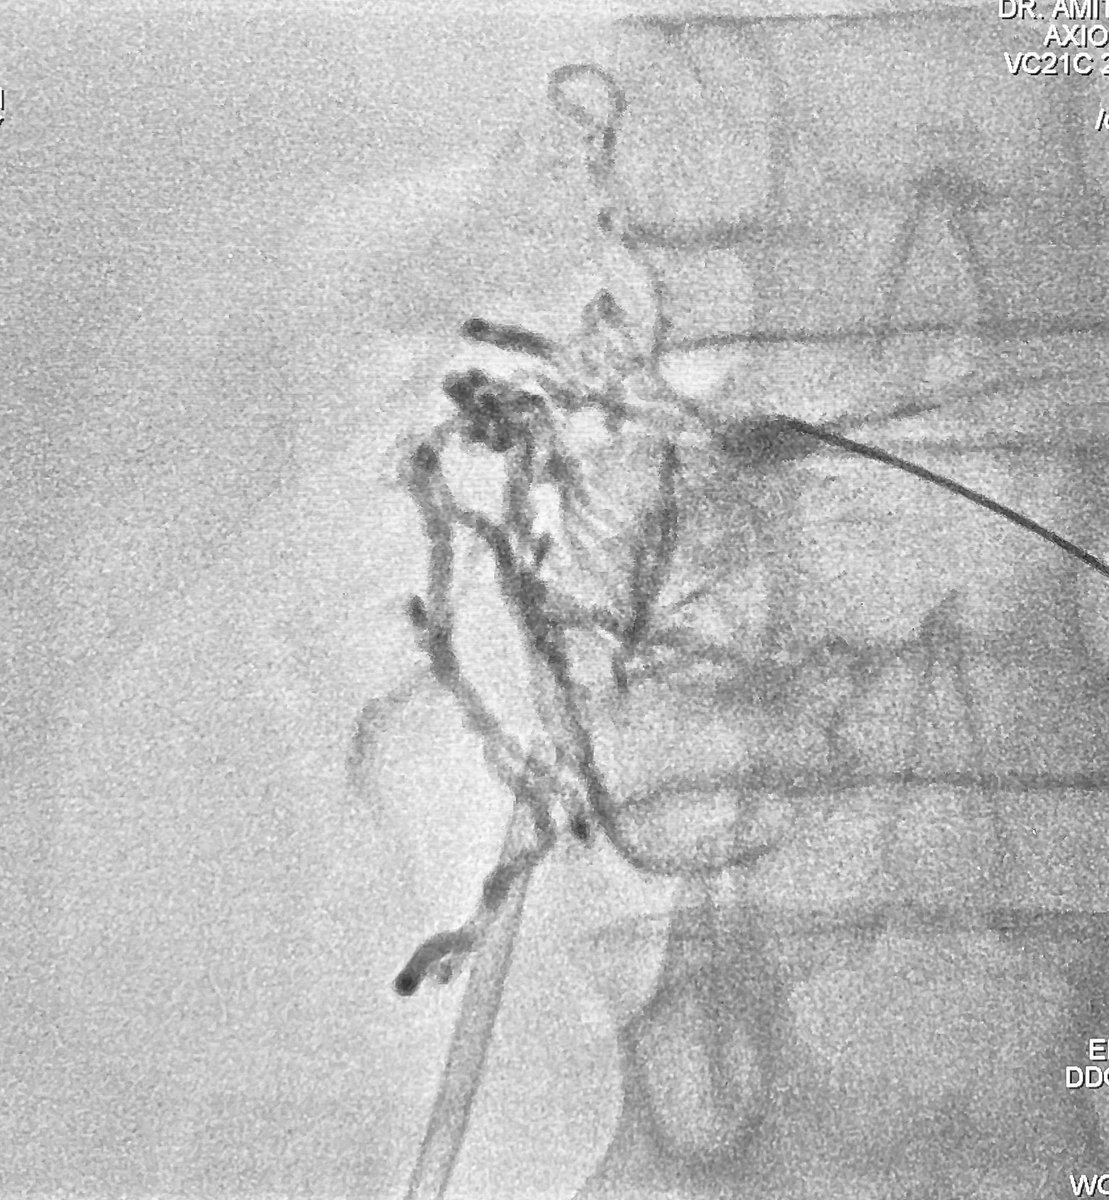

Case : AVM of leg with Pain & Limp.

Rx : AVM Embolization with Glue

#avm #embolization #irad #interventionalradiology #MedTwitter #Mumbai @ISVIRIndia @JVIRmedia @SIRspecialists @SIRRFS @cirsesociety @ApolloHosMumbai